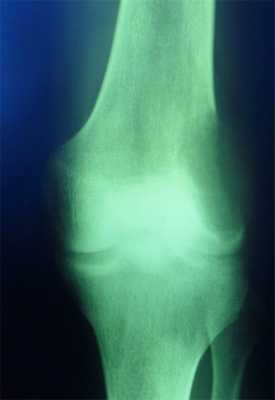

Гигантоклеточная опухоль

(остеобластокластома)

- состоит из клеток 2 типов- многоядерных гигантских и мелких одноядерных,

- поражаются люди в возрасте от 20 до 40 лет,

- локализация бедренная кость - дистальный конец, проксимальный конец б/берцовой кости, дистальный конец лучевой кости. Из плоских костей - тазовые кости и лопатка, очень редкая локализация в позвонках,

- одиночность и изолированность поражения,

- характерно расположение опухоли в эпиметафизраном отделе, который значительно вздут и деформирован, имеет вид крупнобугристого полушария, булавы,

- опухоль доходит до суставного хряща и обрывается,

- растет во всех направлениях, но главный рост происходит вдоль длинной оси кости в сторону с/3 диафиза кости,

- поперечник опухоли может увеличивать нормальный диаметр опухоли в 3-5 раз.

- ячеистый тип - опухоль состоит из отдельных камер, отделенных друг от друга полными и неполными перегородками (мыльные пузыри или неправильные соты),

- корковое вещество раздвигается, вздувается изнутри, истончается, надкостничных наслоений нет,

- при больших опухолях корковое вещество рассасывается и опухоль окружена со всех сторон тонкой скорлупой состоящая из стенок поверхностно расположенных ячеек.

- остеолитический тип - полное отсутствие ячеистого или трабекулярного рисунка, дефект кости вполне гомогенен,

- краевой блюдцеобразный дефект,

- корковый слой на пораженном месте рассасывается, а на границе с дефектом корка заострена, не подрыта и не имеет никаких периостальных наслоений,

- контуры дефекта резкие,

- патологические переломы в 12% случаев.